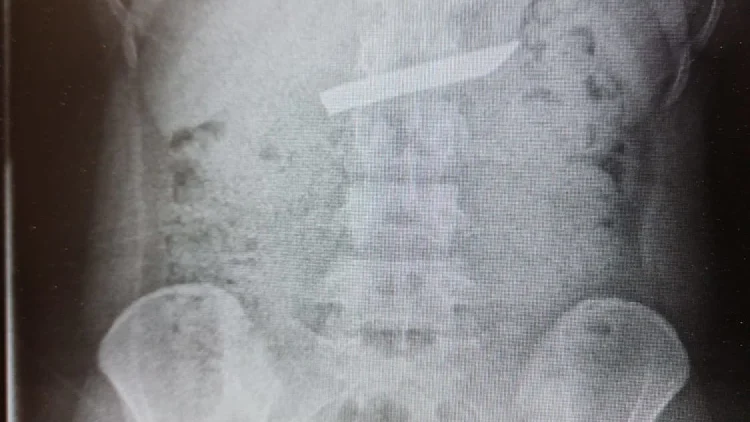

נס רפואי: סכין באורך 9 ס"מ הוצאה השבוע מקיבתה של נערה בת 18, על ידי צוות כירורגי במרכז הרפואי לגליל בנהריה. מדובר בלהב של סכין מטבח בעובי של כ-2 ס"מ, שלדברי הנערה נבלעה במהלך ארוחה.

הנערה, שמתגוררת באחד היישובים בצפון, הגיעה בליווי הוריה למרכז הרפואי כשהיא מתלוננת על כאבים בבטן העליונה וקושי בבליעת מזון. בצילום רנטגן התגלה חפץ גדול בקיבתה, והיא הועברה למכון הגסטרו - אלא שבשל גודלה ועוביה של הסכין, ניתן היה לטפל רק באמצעות הליך כירורגי.

הנערה הועברה בדחיפות לחדר הניתוח במטרה להוציא את הגוף הזר בצורה בטוחה ויעילה. ד"ר כמאל חטיב, סגן מנהל מחלקת כירורגיה א', שלף את להב הסכין מתוך קיבתה באמצעות ציוד אנדוסקופי מתקדם, תוך ביצוע חתך בדופן הקיבה. בתחילה הוצא הלהב בזהירות אל תוך חלל הבטן, ולאחר מכן מחוצה לו. עם תום הניתוח, שנמשך כחצי שעה, הועברה הנערה במצב טוב לאישפוז במחלקת הכירורגיה.